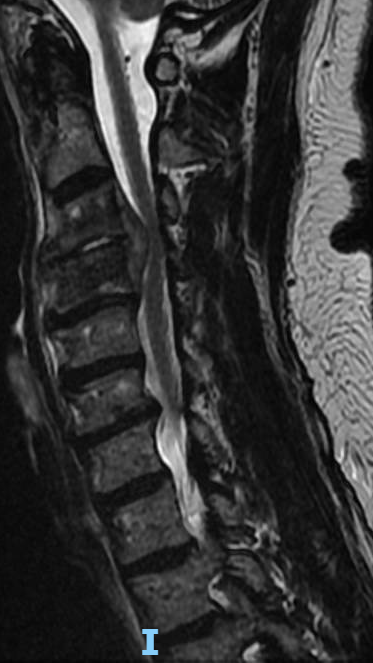

What would your surgical plan be for this patient with a cervical epidural abscess and severe arm weakness? #neurosurgery #physicaltherapy #chiropractor #spine #spinehealth #spinesurgery #cervicalspine

I performed a partial C4 corpectomy with fibular allograft -Abscesses can be more solid than expected -Partial corpectomy offers excellent decompression + stability -Material choice (titanium/allograft/autograft) matters less than thorough I&D and stabilization #cervicalspine